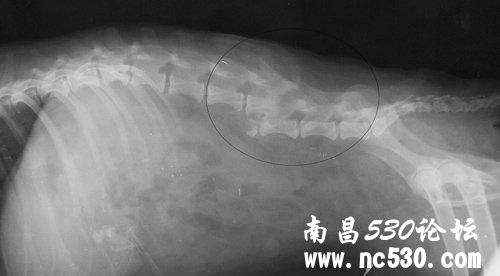

朋友家的萨摩昨天晚上11点左右在小区内被车撞了,晚上出来遛弯狗自己在前面跑着,被撞时没有看到,赶过去也没有发现肇事车辆,当时就失禁了,我们就近找到医院拍了片子,腰椎骨折了,左后腿肿胀,盆骨及腿骨都没有问题,但是医院处理不了腰椎的骨折,打了些止痛消炎的针,用平板抬回家了,现在过去10来个小时了,我们一直没有找到可以处理的宠物医院,也不敢随意移动。请问这种情况应如何处理,北京有没有可以处理的地方? 片子不在我这儿,这个图片是在网上找的,我看着情况差不多,脊椎错位,片子上椎骨可见小碎骨,但是没有像图中这么交叉。